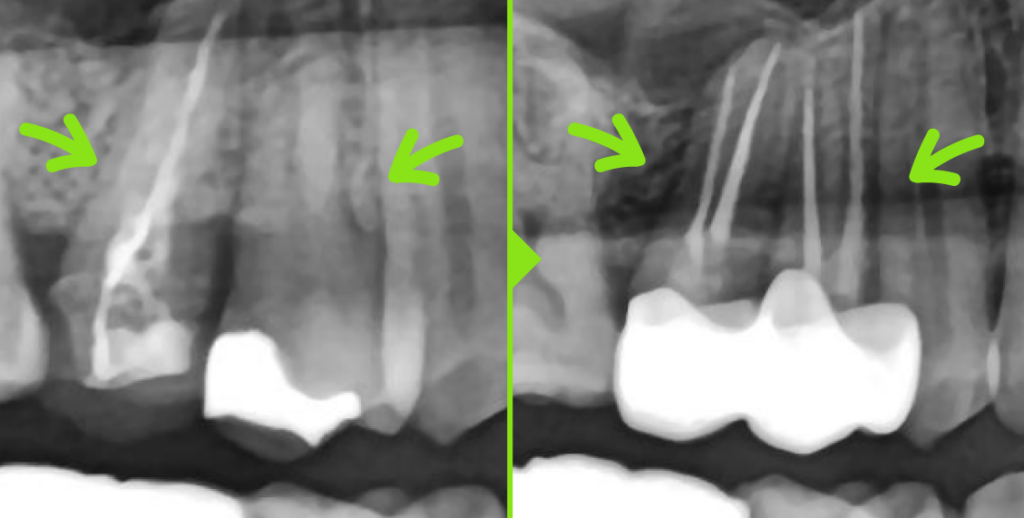

타 치과 신경치료 후 약 6개월이 지난 시점에서

뿌리 끝 염증이 남아 있어 잇몸뼈가 녹은 채로 내원.

재신경치료 진행하였으며,

재신경치료 후 6개월이 지난 시점 사진에서

이전에 보이던 뿌리 주변 염증이 사라지고,

녹았던 잇몸뼈가 다시 차오른

모습을 확인할 수 있었습니다.